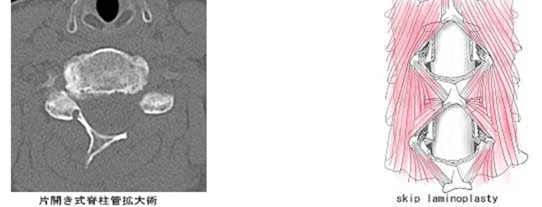

頚椎の後方もしくは前法から神経の通り道を広げます(脊柱管拡大術)。手術用顕微鏡を用いて筋肉をできうる限り温存する、術後の痛みの少ない手術(skip laminoplasty)も施行されています。手術時間は1時間半から3時間、出血はほとんどありません。多くの患者さんが術後1~2週間で退院となります(術前の症状の重症度によって期間は異なります)。